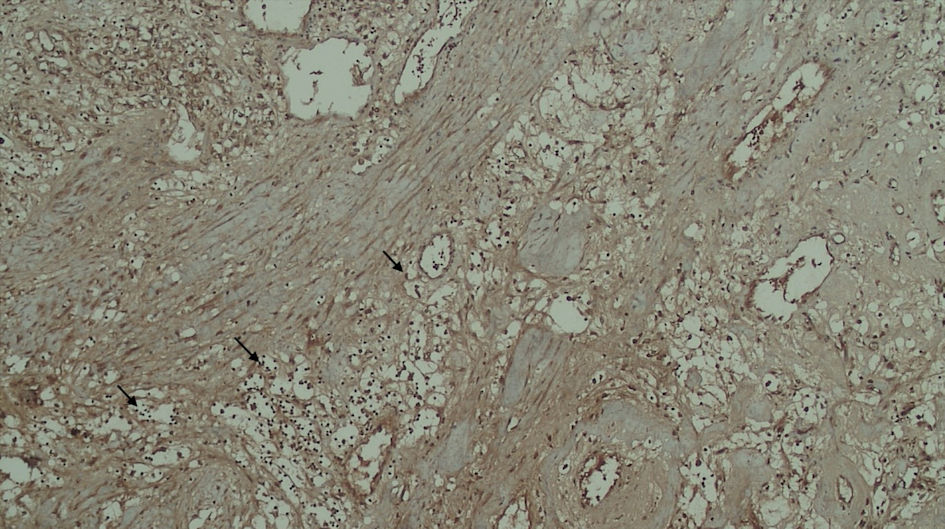

Subjects involved in this research were similar in age. However, most of the subjects involved in this study were male (Table 1). FAP expression correlated positively with TACS despite the tumor being in the stromal or intratumoral (y = 4.5x - 0.6667 in intratumoral tumors, and y = 4.5x - 1.6667 in stromal tumors, as seen in Figure 1). According to the Spearman rho test results, there was a positive correlation between the TACS degree to intratumor samples (96%) and stromal samples (84%), respectively accounted for 25 and 22 patients (y = 0.5x + 0.8; P = 0.0001) (Fig. 2). Histopathological images of TAC-3 collagen deposits (Fig. 3), and positive intratumoral and stromal FAP are illustrated below (Figs. 4, 5).

![]() Click for large image | Figure 4. Positive FAP expression in the tumor cell (black arrow). FAP: fibroblast activation protein. |

FAP is a marker of activated fibroblasts, which is found to be more abundant in tumors with invasive and aggressive phenotypes than those in noninvasive and nonaggressive types. Studies have suggested that FAP expression is associated with poorer prognosis. The effect of malignancy in mCCRCC can be detected by using TACS grading, which can be assessed by the changes in collagen structure; thus, these changes could be used as a prediction for the invasiveness of mCCRCC [8].

Based on our findings, we try to describe the FAP expression prevalence rate both in the stroma and intratumor of mCCRCC patients. Other studies have shown that FAP presence in mCCRCC patients is correlated with high stage, higher grade, and necrotic tumors with 10-years survival. Furthermore, the majority of the intratumor and stromal samples were found to have positive FAP expression, implying a poorer prognosis among a majority of the patients in our center and a prevalence of FAP. This finding is in line with another study that found that immunostaining FAP is 100% found in patients with sarcomatoid RCC [14].